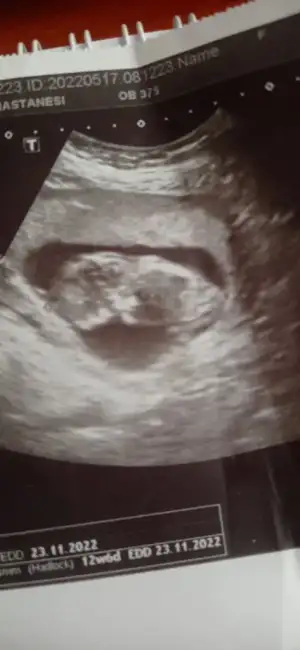

prenses gibi12+6 karından ultrason